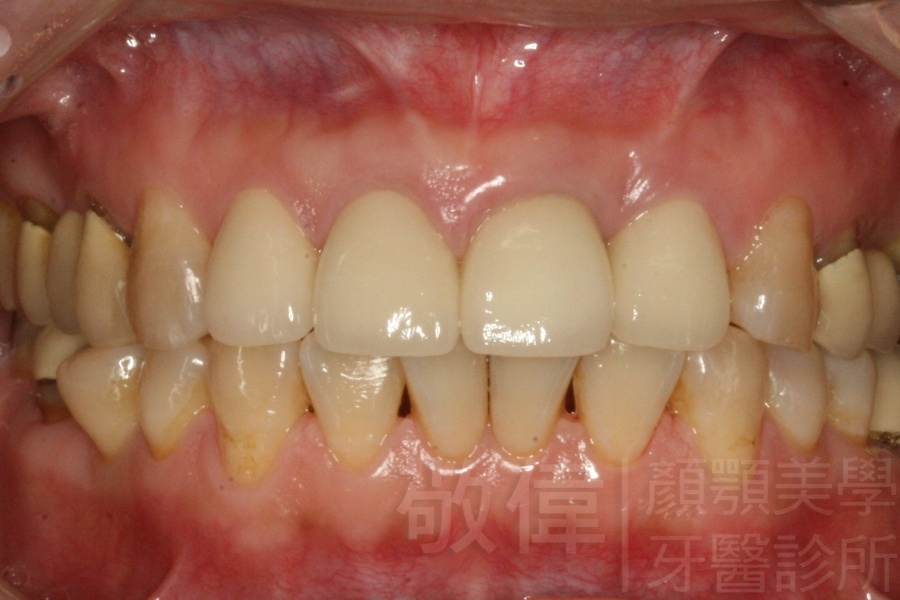

人工植牙/全口咬合植牙重建

治療前上顎   治療前正面   治療前下顎

治療後上顎   治療後正面   治療後下顎